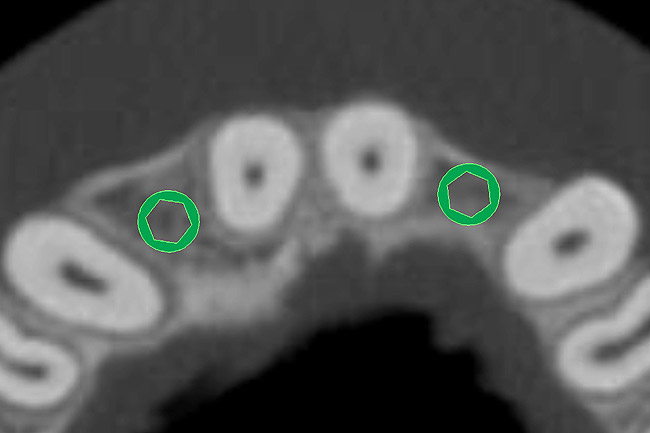

The CT axial views represent an important instrument in gaining a better understanding of anatomical features that can not be determined by any other imaging modality (Figure 6A). When the maxilla is sliced axially at the level where the roots meet the crest of the bone, the adjacent and surrounding root morphology can be revealed. Of note are the individual and different shapes of each of the central incisors, canines, premolars, and molar roots. These images reflect a phenomenon defined by the author as the “restorative dilemma.” Clinicians encounter this often difficult dilemma when attempting to re-establish morphologically correct emergence profiles in prosthetic teeth as they ascend from the round shape of the implant(s). When planning for the placement of the implant in the left lateral incisor area, there appeared to be adequate mesial-distal space between roots as seen in the axial view of Figure 6B. A closer inspection of the planned site for the right lateral incisor revealed a more narrow space, further.complicated by the distal rotation of the palatal aspect of the tooth root. Based on this preliminary position, the 3.75-mm diameter, straight-walled implant can be seen encroaching on the lamina dura periodontal ligament space of the right canine and central incisor. If there was not adequate room for this diameter and type of implant, the adjacent teeth could sustain potential iatrogenic damage. Therefore, additional “tweaking” of the virtual placement was necessary to diminish this risk.

Figure 6a  By slicing the maxilla axially, the images revealed (A) the differing morphology of the central incisors, canines, premolar, and molar roots, and (B) the left simulated implant seen encroaching on the adjacent lamina dura.

Figure 6a

Figure 6b  By slicing the maxilla axially, the images revealed (A) the differing morphology of the central incisors, canines, premolar, and molar roots, and (B) the left simulated implant seen encroaching on the adjacent lamina dura.

Figure 6b